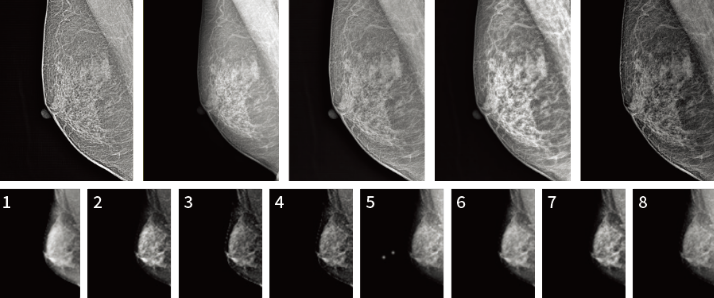

다양한 영상 타입 제공(Film / CR / FFDM)으로 사용자 만족도 향상

피부 표현 극대화, 미세석회화 증폭 기술을 통한 병변 검출 효과 향상

다양한 필터 효과를 통해 사용자가 직접 쉽고 빠르게 최적화된 영상 선택